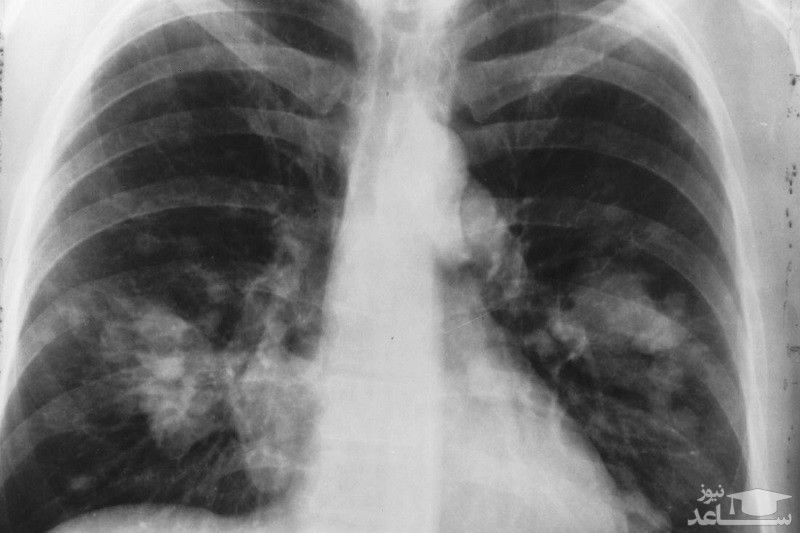

کریزوتینیب (Crizotinib) با نام تجاری زالکوری (Xalkori) یک داروی ضد سرطان می باشد که از رشد و گسترش سلول های سرطانی در بدن جلوگیری می کند. این دارو برای درمان انواع خاصی از سرطان ریه و سرطان ریه سلول غیر کوچک (NSCLC) که به سایر نقاط بدن گسترش یافته استفاده می شود.

کریزوتینیب متعلق به داروهای مهار کننده کیناز است که برای درمان سرطان ریه استفاده می شود. این دارو با کاهش یا توقف رشد سلول های سرطانی ریه کار می کند.